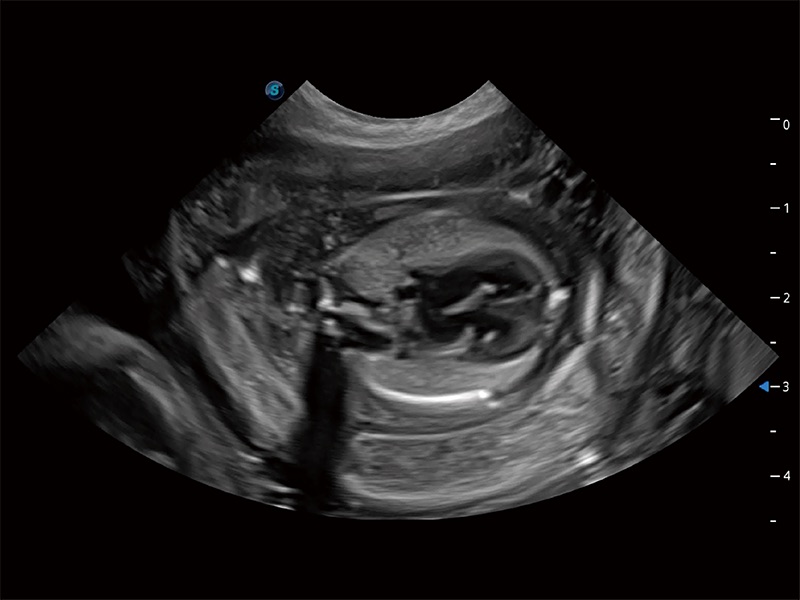

(犬)四腔心MQA

(犬)胎儿四腔心

(猫)二尖瓣M型

(犬)二腔心血流